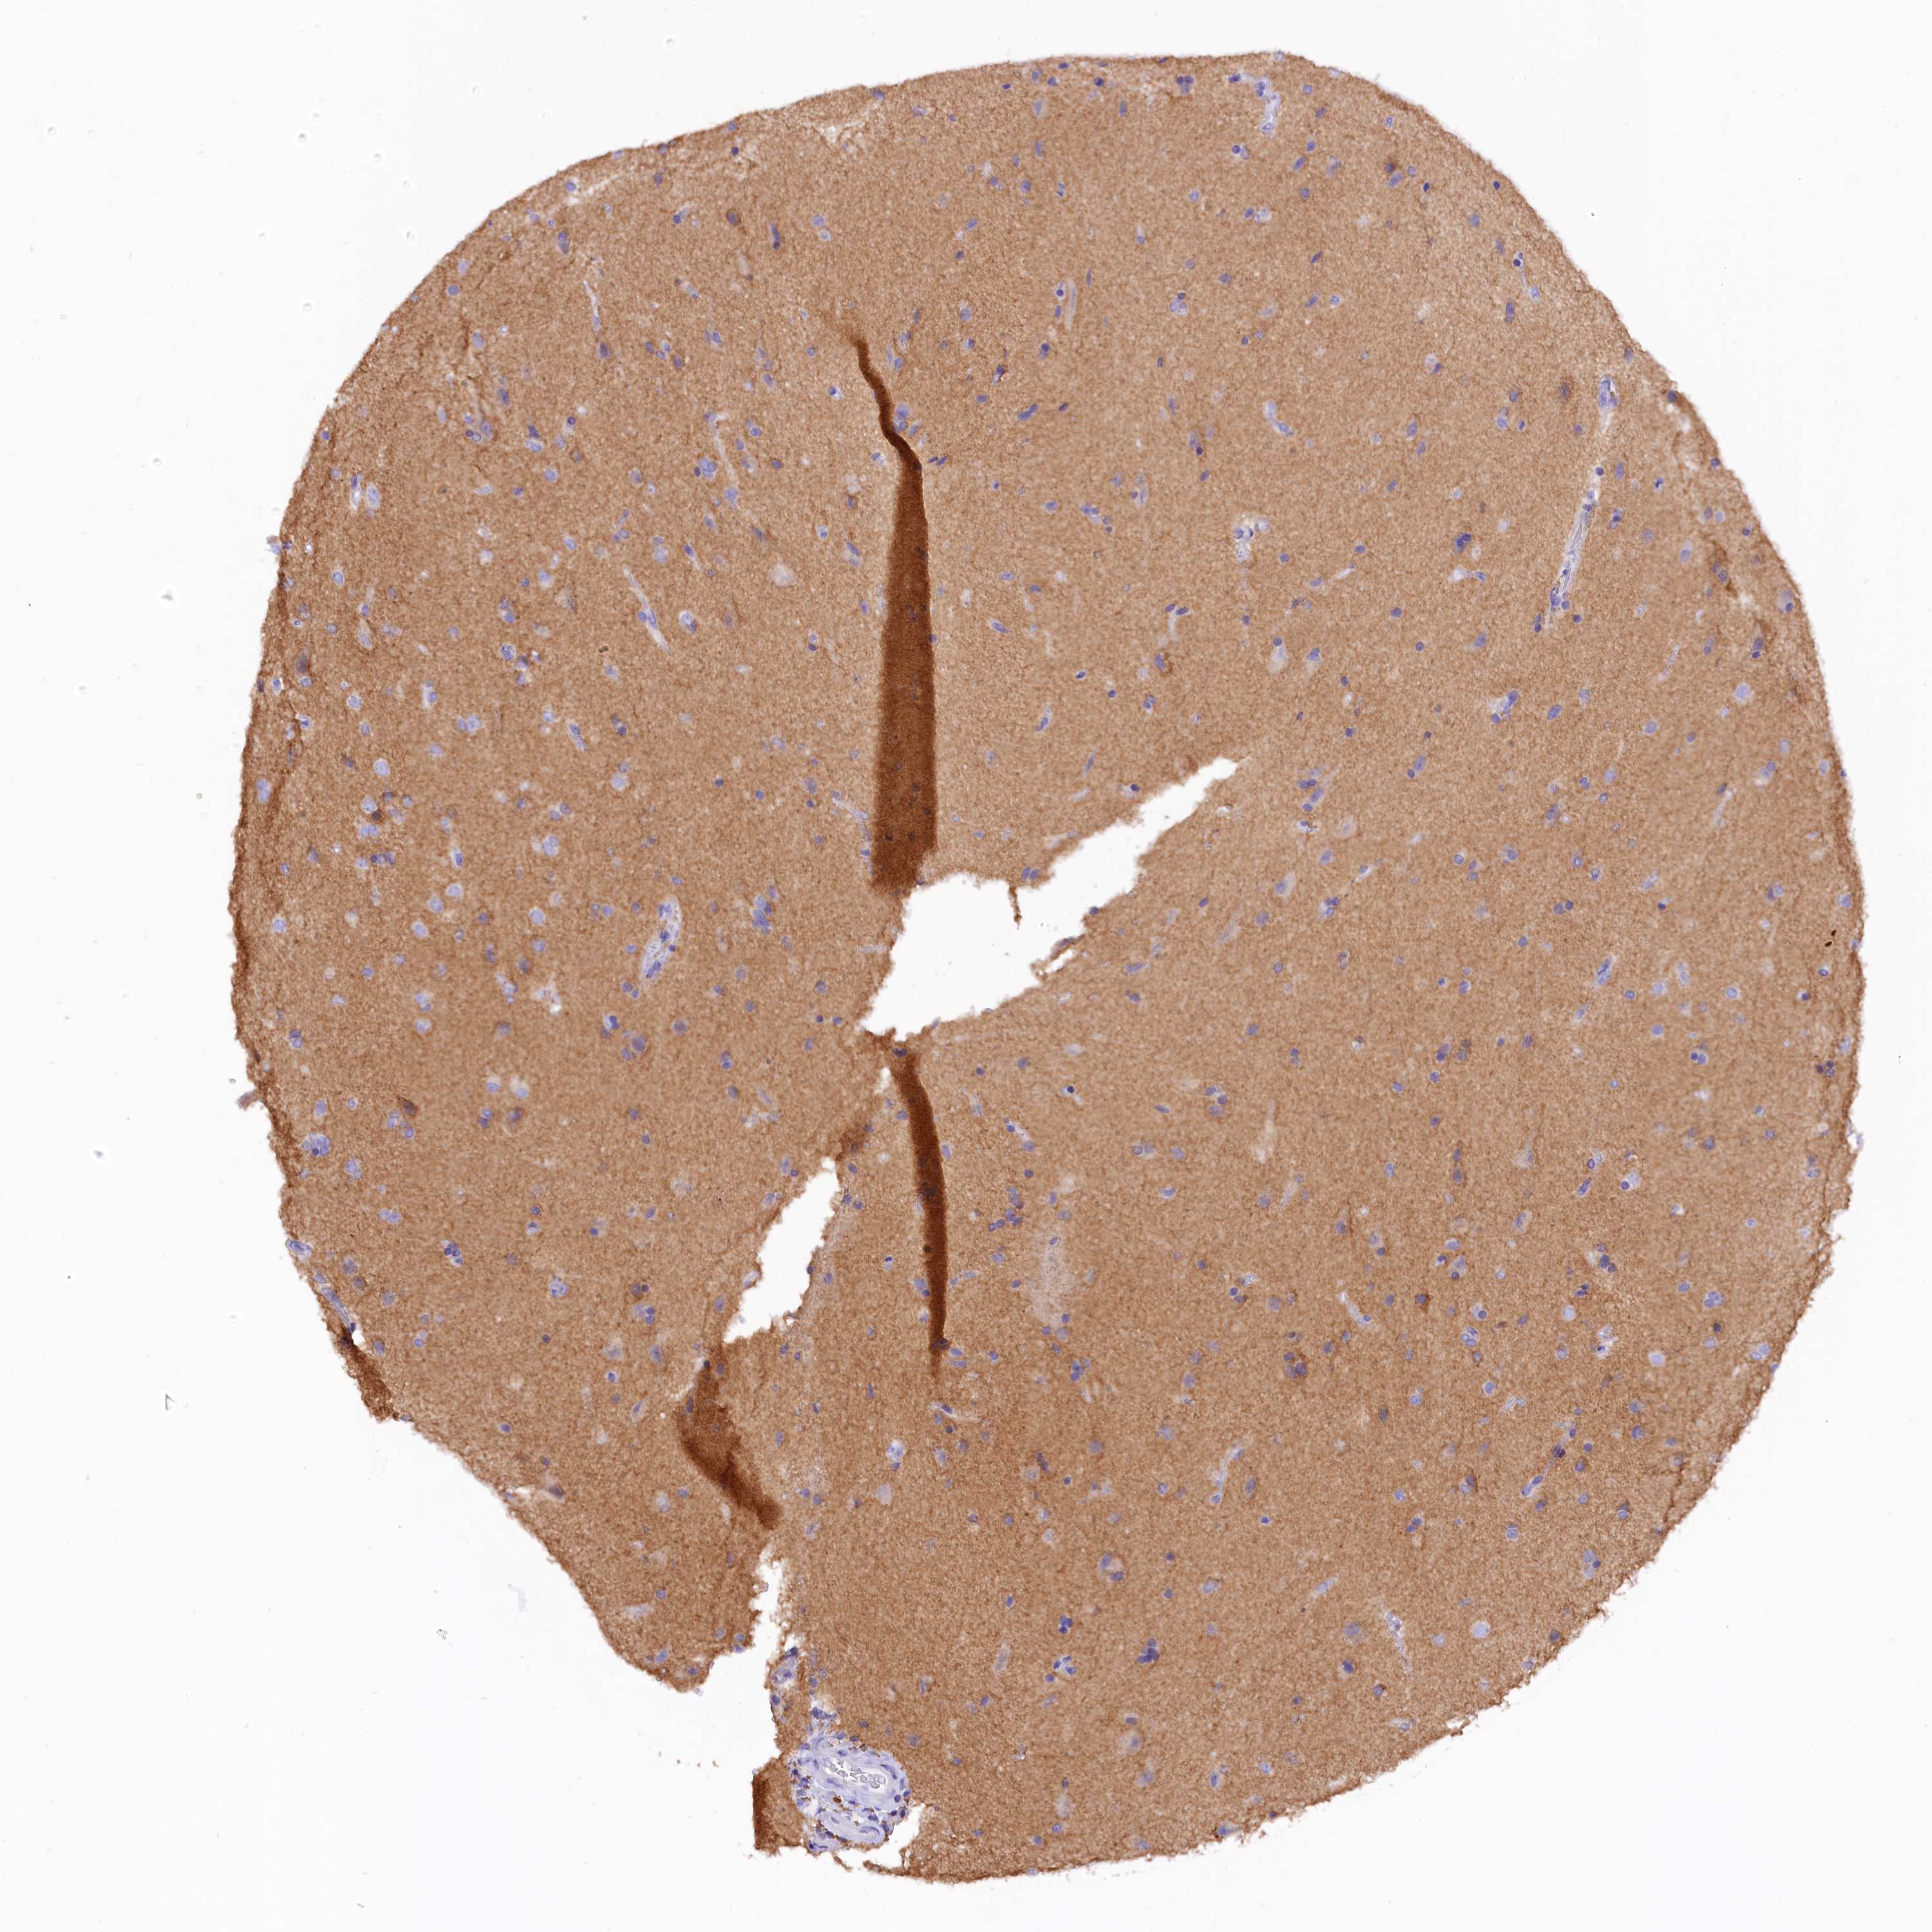

GLIOMA - Protein expressioni

A mouse-over function shows sample information and annotation data. Click on an image to view it in a full screen mode. Samples can be filtered based on level of antibody staining by selecting one or several of the following categories: high, medium, low and not detected. The assay and annotation is described here.

Antibody stainingi

Antibody staining in the annotated cell types in the current human tissue is reported as not detected, low, medium, or high, based on conventional immunohistochemistry profiling in selected tissues. This score is based on the combination of the staining intensity and fraction of stained cells.

Each image is clickable and will lead to virtual microscopy that enables deeper exploration of all samples and also displays staining intensity scores, fraction scores and subcellular localization as well as patient and tissue information for each sample.

Antibody HPA043138

Staining

High

Medium

Low

Not detected

Intensity

Strong

Moderate

Weak

Negative

Quantity

>75%

75%-25%

<25%

None

Location

Nuclear

Cytoplasmic/membranous

Cytoplasmic/membranous,nuclear

Glioma, malignant, High grade

Glioma, malignant, Low grade